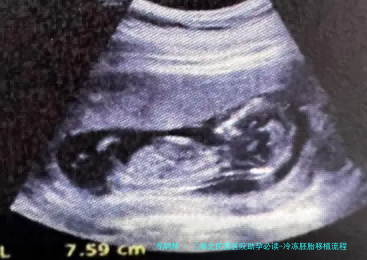

冷冻胚胎移植是一项邃密化的生殖诊疗技术,整个过程须要医生准确把握移植时机。其核心在于保证胚胎形成与子宫内膜发育的同步进程,为胚胎着床创造最完美条件。

在移植当日,实践室医生会将挑选的冷冻胚胎冻结,并评估其存活情况和质量。随之在B超引导下,医生使用一根细软管将胚胎精准放置到子宫腔内最完美位置。移植后,病人须要遵医嘱使用黄体支持药物,直至移植后十日至十四日进行验孕。